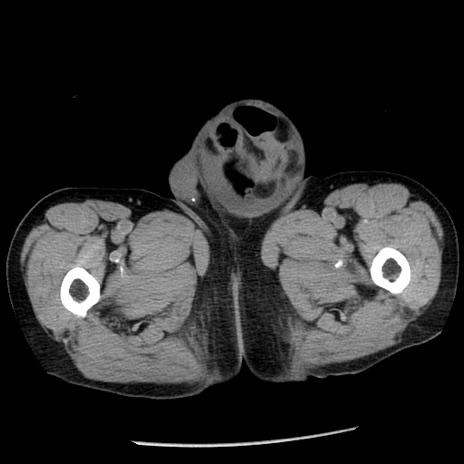

症例26(横断像)

【症例】80歳代男性

【主訴】嘔吐

【現病歴】昨晩2回嘔吐あり、今朝になっても嘔吐あり。来院。

【既往歴】胃潰瘍

【身体所見】意識清明、BT 37.6℃、BP 166/95mmHg、HR 100bpm、SpO2 97%、腹部:平坦・軟、腸蠕動音聴取良好、圧痛なし。

【データ】WBC 21900、CRP 1.46